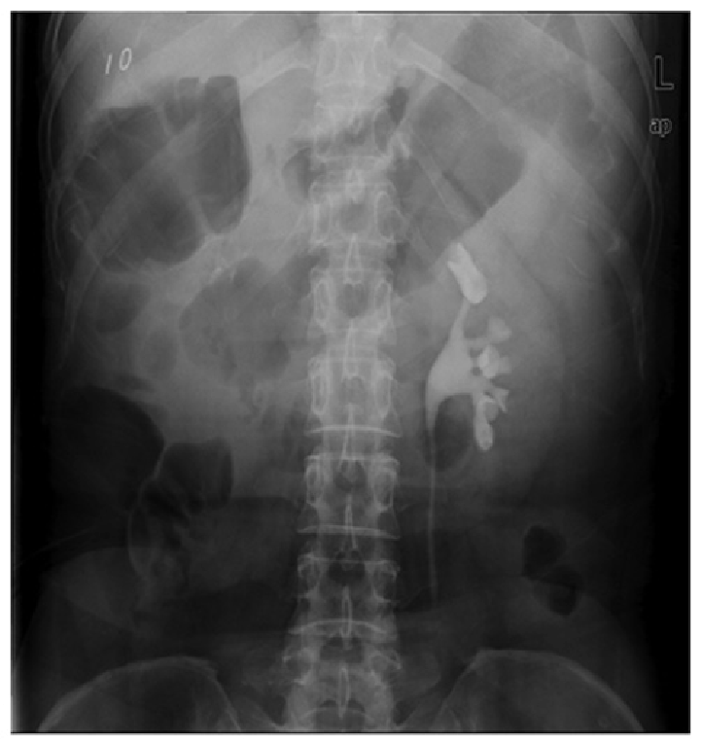

X-ray shows multiple round, calcified densities with radiolucent centers in the pelvis.

Differentiation:

Phlebolith shows central lucency (donut sign).

Lies lateral to ureteric course.